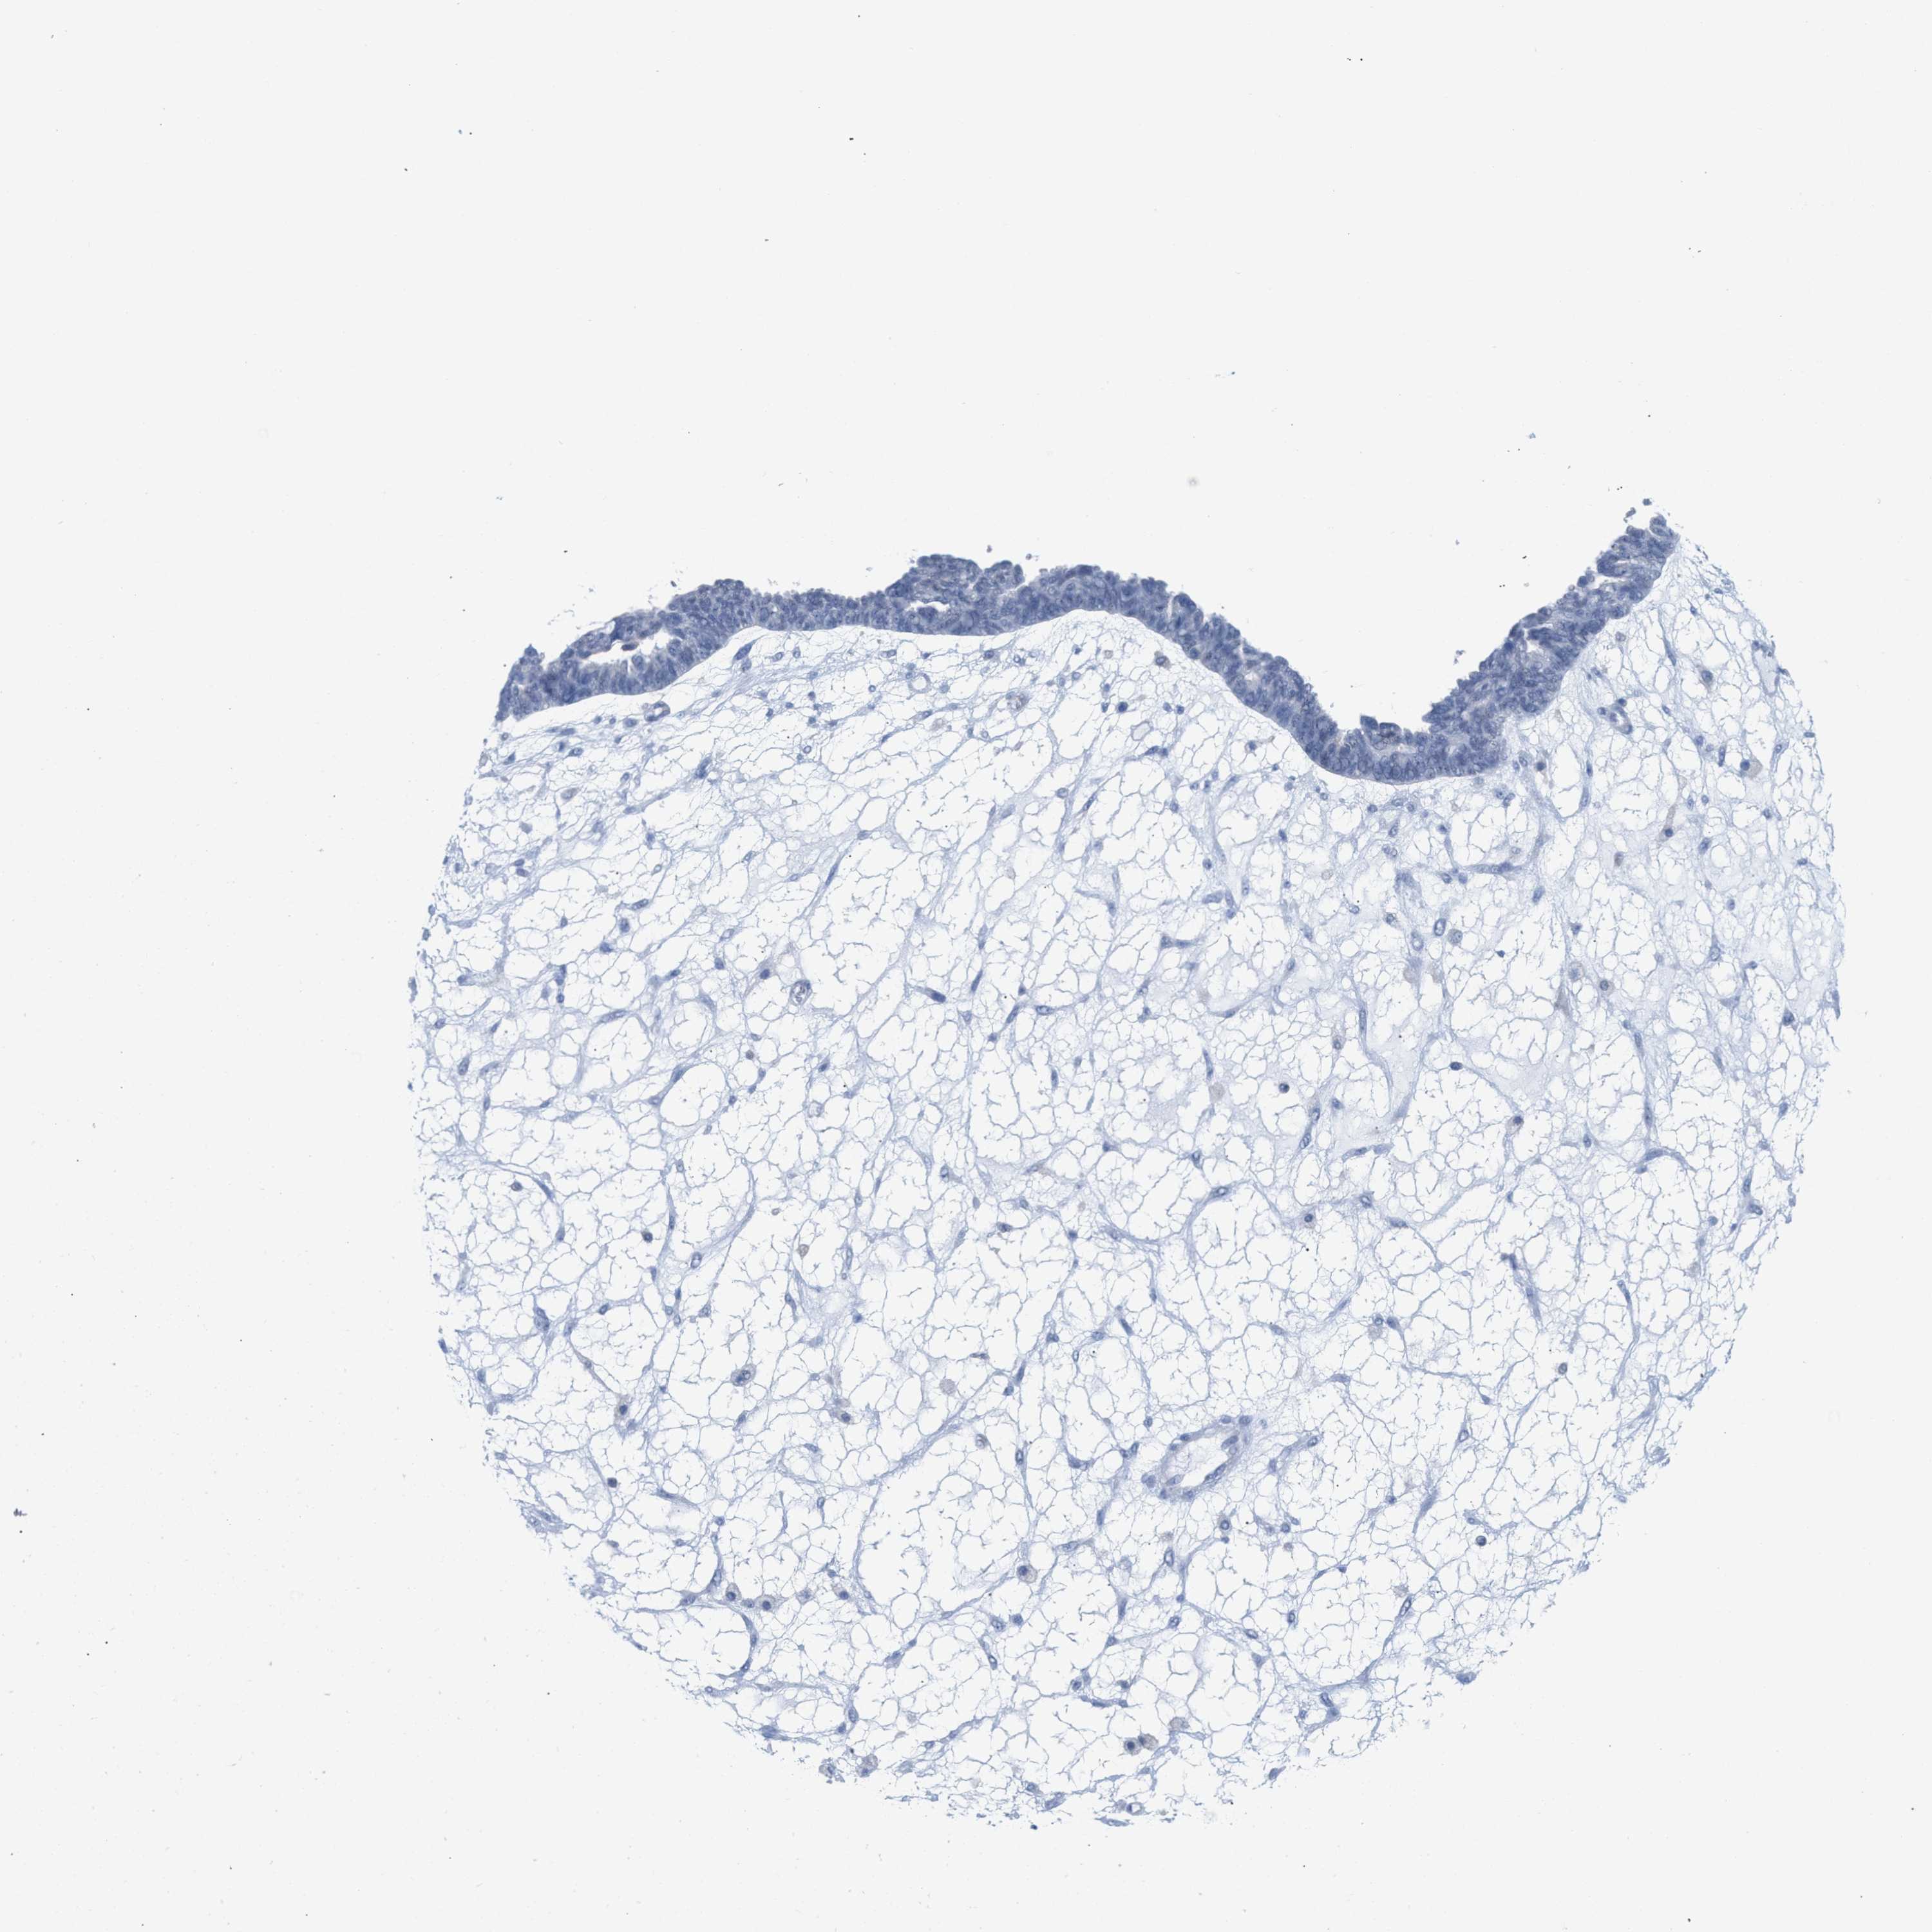

OVARIAN CANCER - Protein expressioni

A mouse-over function shows sample information and annotation data. Click on an image to view it in a full screen mode. Samples can be filtered based on level of antibody staining by selecting one or several of the following categories: high, medium, low and not detected. The assay and annotation is described here.

Note that samples used for immunohistochemistry by the Human Protein Atlas do not correspond to samples in the TCGA dataset.

Antibody stainingi

Antibody staining in the annotated cell types in the current human tissue is reported as not detected, low, medium, or high, based on conventional immunohistochemistry profiling in selected tissues. This score is based on the combination of the staining intensity and fraction of stained cells.

Each image is clickable and will lead to virtual microscopy that enables deeper exploration of all samples and also displays staining intensity scores, fraction scores and subcellular localization as well as patient and tissue information for each sample.

Antibody HPA018467

Antibody CAB005247

Cystadenocarcinoma, serous, NOS

Carcinoma, endometroid

Cystadenocarcinoma, mucinous, NOS

Carcinoma, NOS